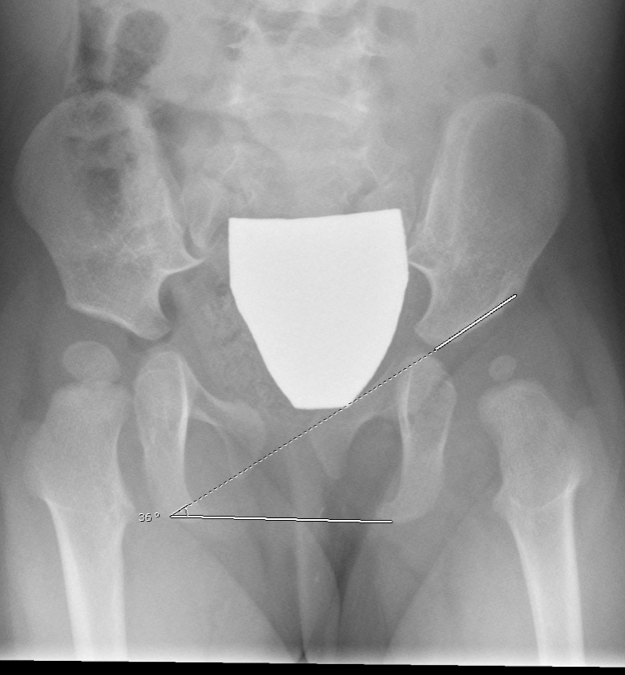

A 49yearold female DDH case of hip arthroplasty with HPF stem Old Ddh Radiology developmental dysplasia of the hip (ddh) is one of the most common musculoskeletal problems in newborns. Because of their low cost and ready accessibility, radiographs are the primary. — radiographic findings. — developmental dysplasia of the hip (ddh) is a disorder of abnormal development resulting in dysplasia,. — developmental dysplasia of the hip (ddh), or in. Old Ddh Radiology.